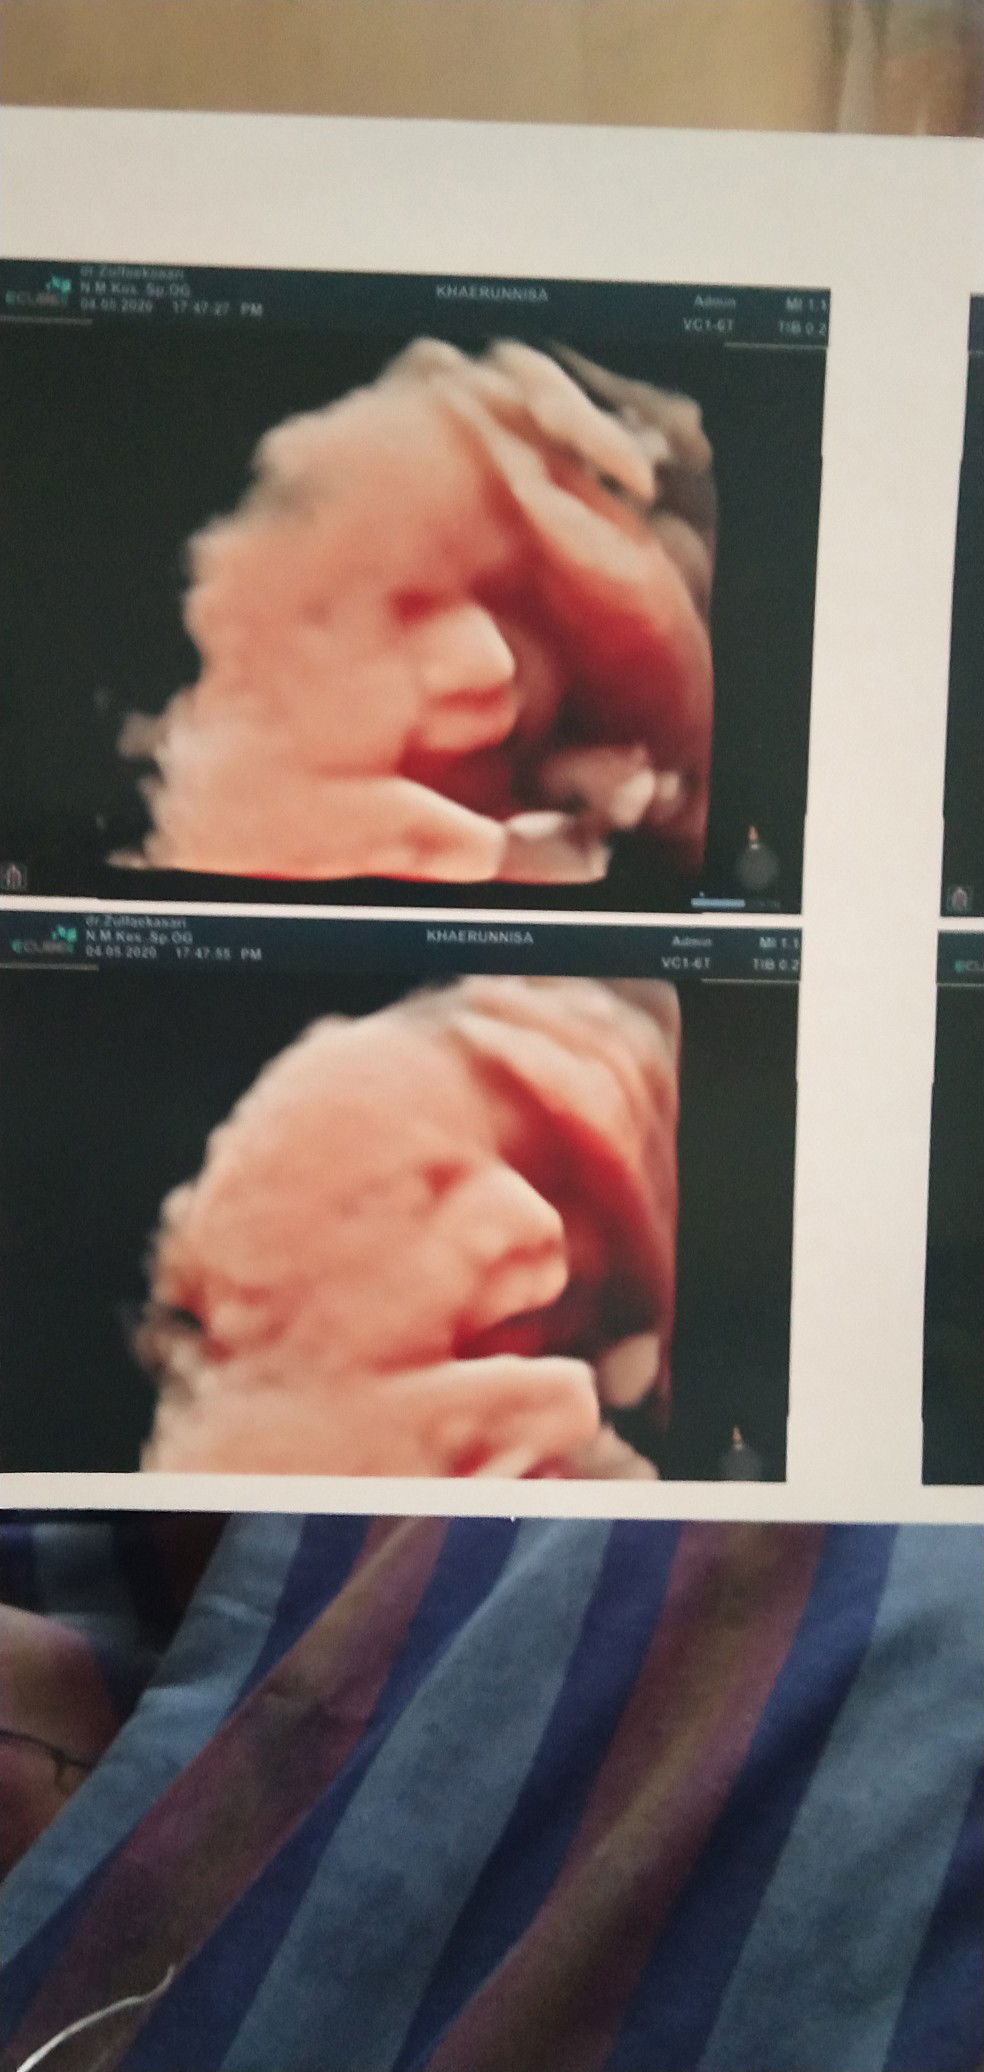

Masih bingung dgn hpl,, waktu pertama kali usg itu di Uk 26W hpl nya 2 juli (ini aku usgnya dibidan yah bun) trus krn waktu itu posisi janin sungsang aku disuruh banyakin sujud dan kembali usg kalau udh sebulan ( 30Weeks) buat nge cek posisi janinx udh berubah atau belum,,, nah aku pergi usg (di dokter) pas uk 31W 😅,, dan ternyata pas diusg uk udah masuk 33W dan hpl berubah mjadi 18 juni (besok tpatnya) (foto ke 1) yah aku gantilah uk ku jadi 33W,, Nahh, pas aku pergi usg lagi di uk 37W (didokter yg sama) ehh Hpl nya berubah lagi dong, jadi 28 juni (foto ke 2).. Jadi ceritanya uk juga otomatis berubah jadi 36W Dong? Tapi dokternya sempat bilang "klw dd nya belum lahir sampai 3 pekan yg akan datang, agak bahaya nih" Trus aku itung dari tanggal itu (1 juni) sampai 3 pekan yg akan datang itu cuman sampai tgl 20 junii bunn 🥴🥴 Haduhh jadi bingung kan aku,, bukan apanya yahh,, yg namanya Hpl juga perlu diketahui supaya ada kesiapan gitu bunn,, Adduhh biar lebih jelasx Usg pertama Hpl (2 juli) Usg ke 2 (18 juni) Usg ke 3 (28 juni) Hpht 18 sept 2019 Mohon bantu infox yahh bunn,,